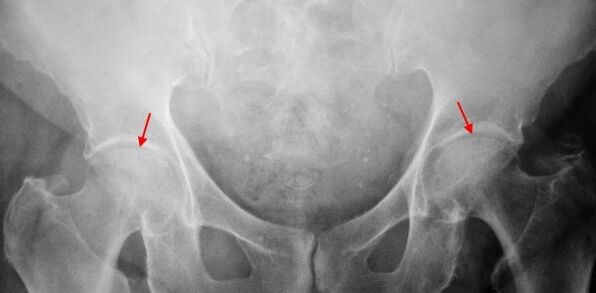

Mild changes in the patient suffering from COXARTROZ 1, the gentleman is a moderate narrow narrow, as well as bone growth around the foreign or inner edge of the form of the femur.

The 2nd rate in X -Ray photos is determined by a joint cavity (more than half).The femoral head changes slightly upwards, deformed and increases in size and its contours are uneven.In this extent, the bone growths appear only on the outside of the acetabulum and appear outside the cartilage.

The 3rd degree was found in radiographs, thigh heads and more than one bone growth in radiographs for the sharp contraction of the 3rd degree, a joint venture.

Coxarthroz diagnosis is based on clinical signs and data of the main work, the main radiography.In many cases, X -Rays allow you to identify the reason for the fact that it is not only a code of codromrosis, but at the same time.Thus, the brain shows the growth, acetabulum scenes and plainness of acethallum and changes in the form of the proximal part of the females, coksartrosis is a result of permetic disease or young epipholysis.COXARTRAZRAZRATIES Changes in infidel-radiographs can also be detected.